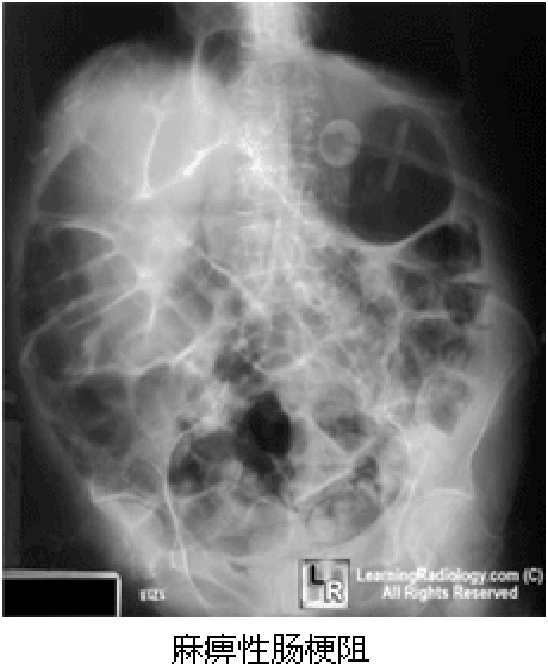

(1)腹部X线平片可显示肠麻痹;

呈阵发性腹痛伴便秘,不排气,疼痛位于脐周及下腹部, 肠鸣音亢进并可闻及气过水声。腹部X线检查可见液气平面。